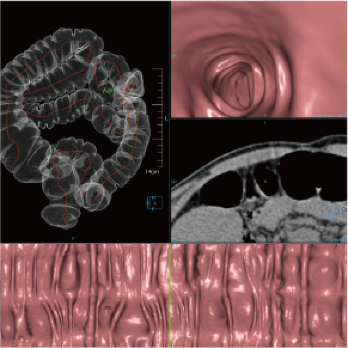

3 core components built on a new industry-leading configuration

Large-capacity tube delivers exceptional stability and durability, ensuring consistently high-quality output even under heavy workloads

High-power generator delivers high mA output for rapid scanning of complex anatomy and large coverage areas, boosting scan speed while enhancing image signal-to-noise ratio and minimizing artifacts

Wide detector expands single-rotation coverage, shortens exam time, reduces motion artifacts, decreases radiation dose, and saves tube exposure time while effectively lowering operating costs